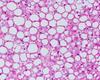

What type of tumour are these images? Describe why.

Adenocarcinoma

- Mucin stain with glands - show up blue

- Dark irregular nuclei still froming gland-like structure